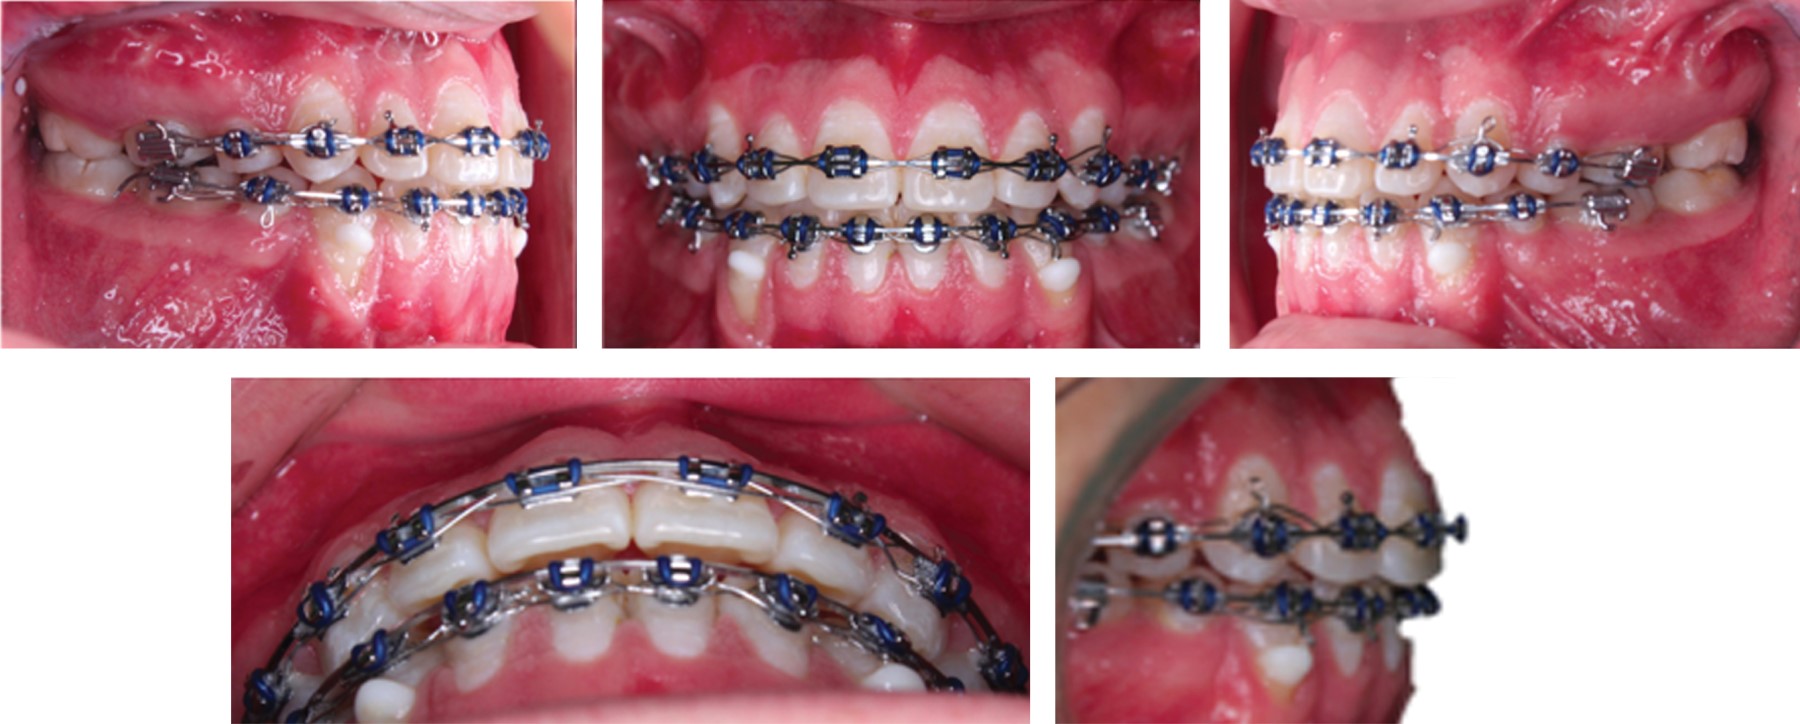

Durante la fase ortopédica se realizó la colocación de las placas de anclaje esqueletal de 2.0 mm de titanio, cada una con dos tornillos de 2.0 × 9 mm colocados en la parte mandibular entre caninos y laterales de ambos lados y en la parte maxilar en el arco cigomático a nivel radicular del segundo molar en ambos lados, el cual es un procedimiento realizado con anestesia general, pero ambulatorio. Al mes del procedimiento quirúrgico se toma una tomografía de haz cónico (Cone Beam) para la evaluación de la osteointegración de las placas y posteriormente hacer la colocación de elásticos clase III con 150 g de fuerza (Figura 4A), en esta fase del tratamiento se colocan turbo bite en primeros molares superiores para lograr la desoclusión anterior y que la mecánica fuera más efectiva junto con los elásticos clase III que se utilizaron por 10 meses (Figura 4B), comenzando con fuerzas ligeras desde los 150 g hasta llegar a los 450 g por lado. Posterior a esto, el paciente presentó una mejor relación maxilomandibular y se continuó con la fase ortodóncica para la corrección de la oclusión (Figura 5).

Figura 5